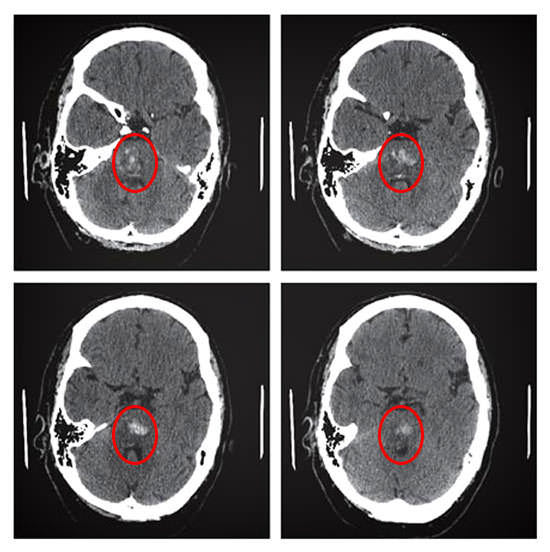

Однако для определения характера нарушения, степени сдавливания окружающих тканей, отека мозга требуются вспомогательные исследования. Самый быстрый способ исключить кровоизлияние – компьютерная томография мозга. Ее проводят первой. Если геморрагическая природа инсульта не подтверждаются, больного направляют на магнитно-резонансную томографию – лучший способ диагностики ишемической формы.